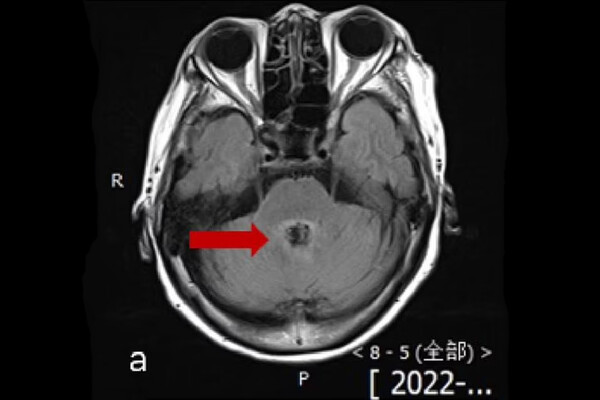

77-летняя пациентка обратилась в местную больницу в 2022 году с жалобами на головокружение, растерянность и трудности с речью, которые продолжались несколько дней. На снимках мозга врачи обнаружили поражение, которое могло быть раком. Однако анализ спинномозговой жидкости (образец получили с помощью укола в поясницу) показал, что пациентка была заражена одноклеточной амебой Balamuthia mandrillaris.